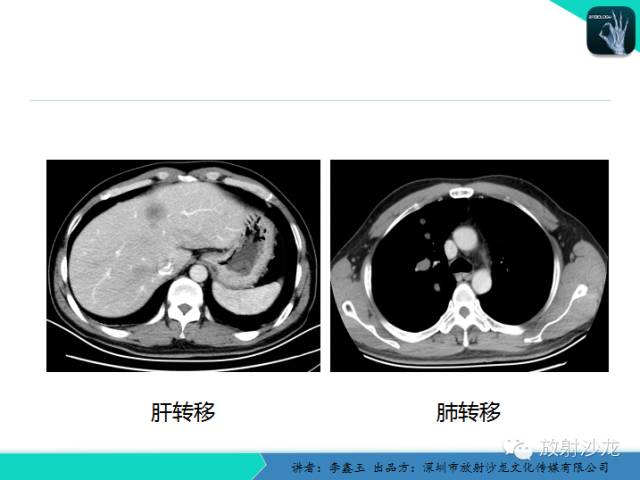

CT在食管癌诊疗中的应用